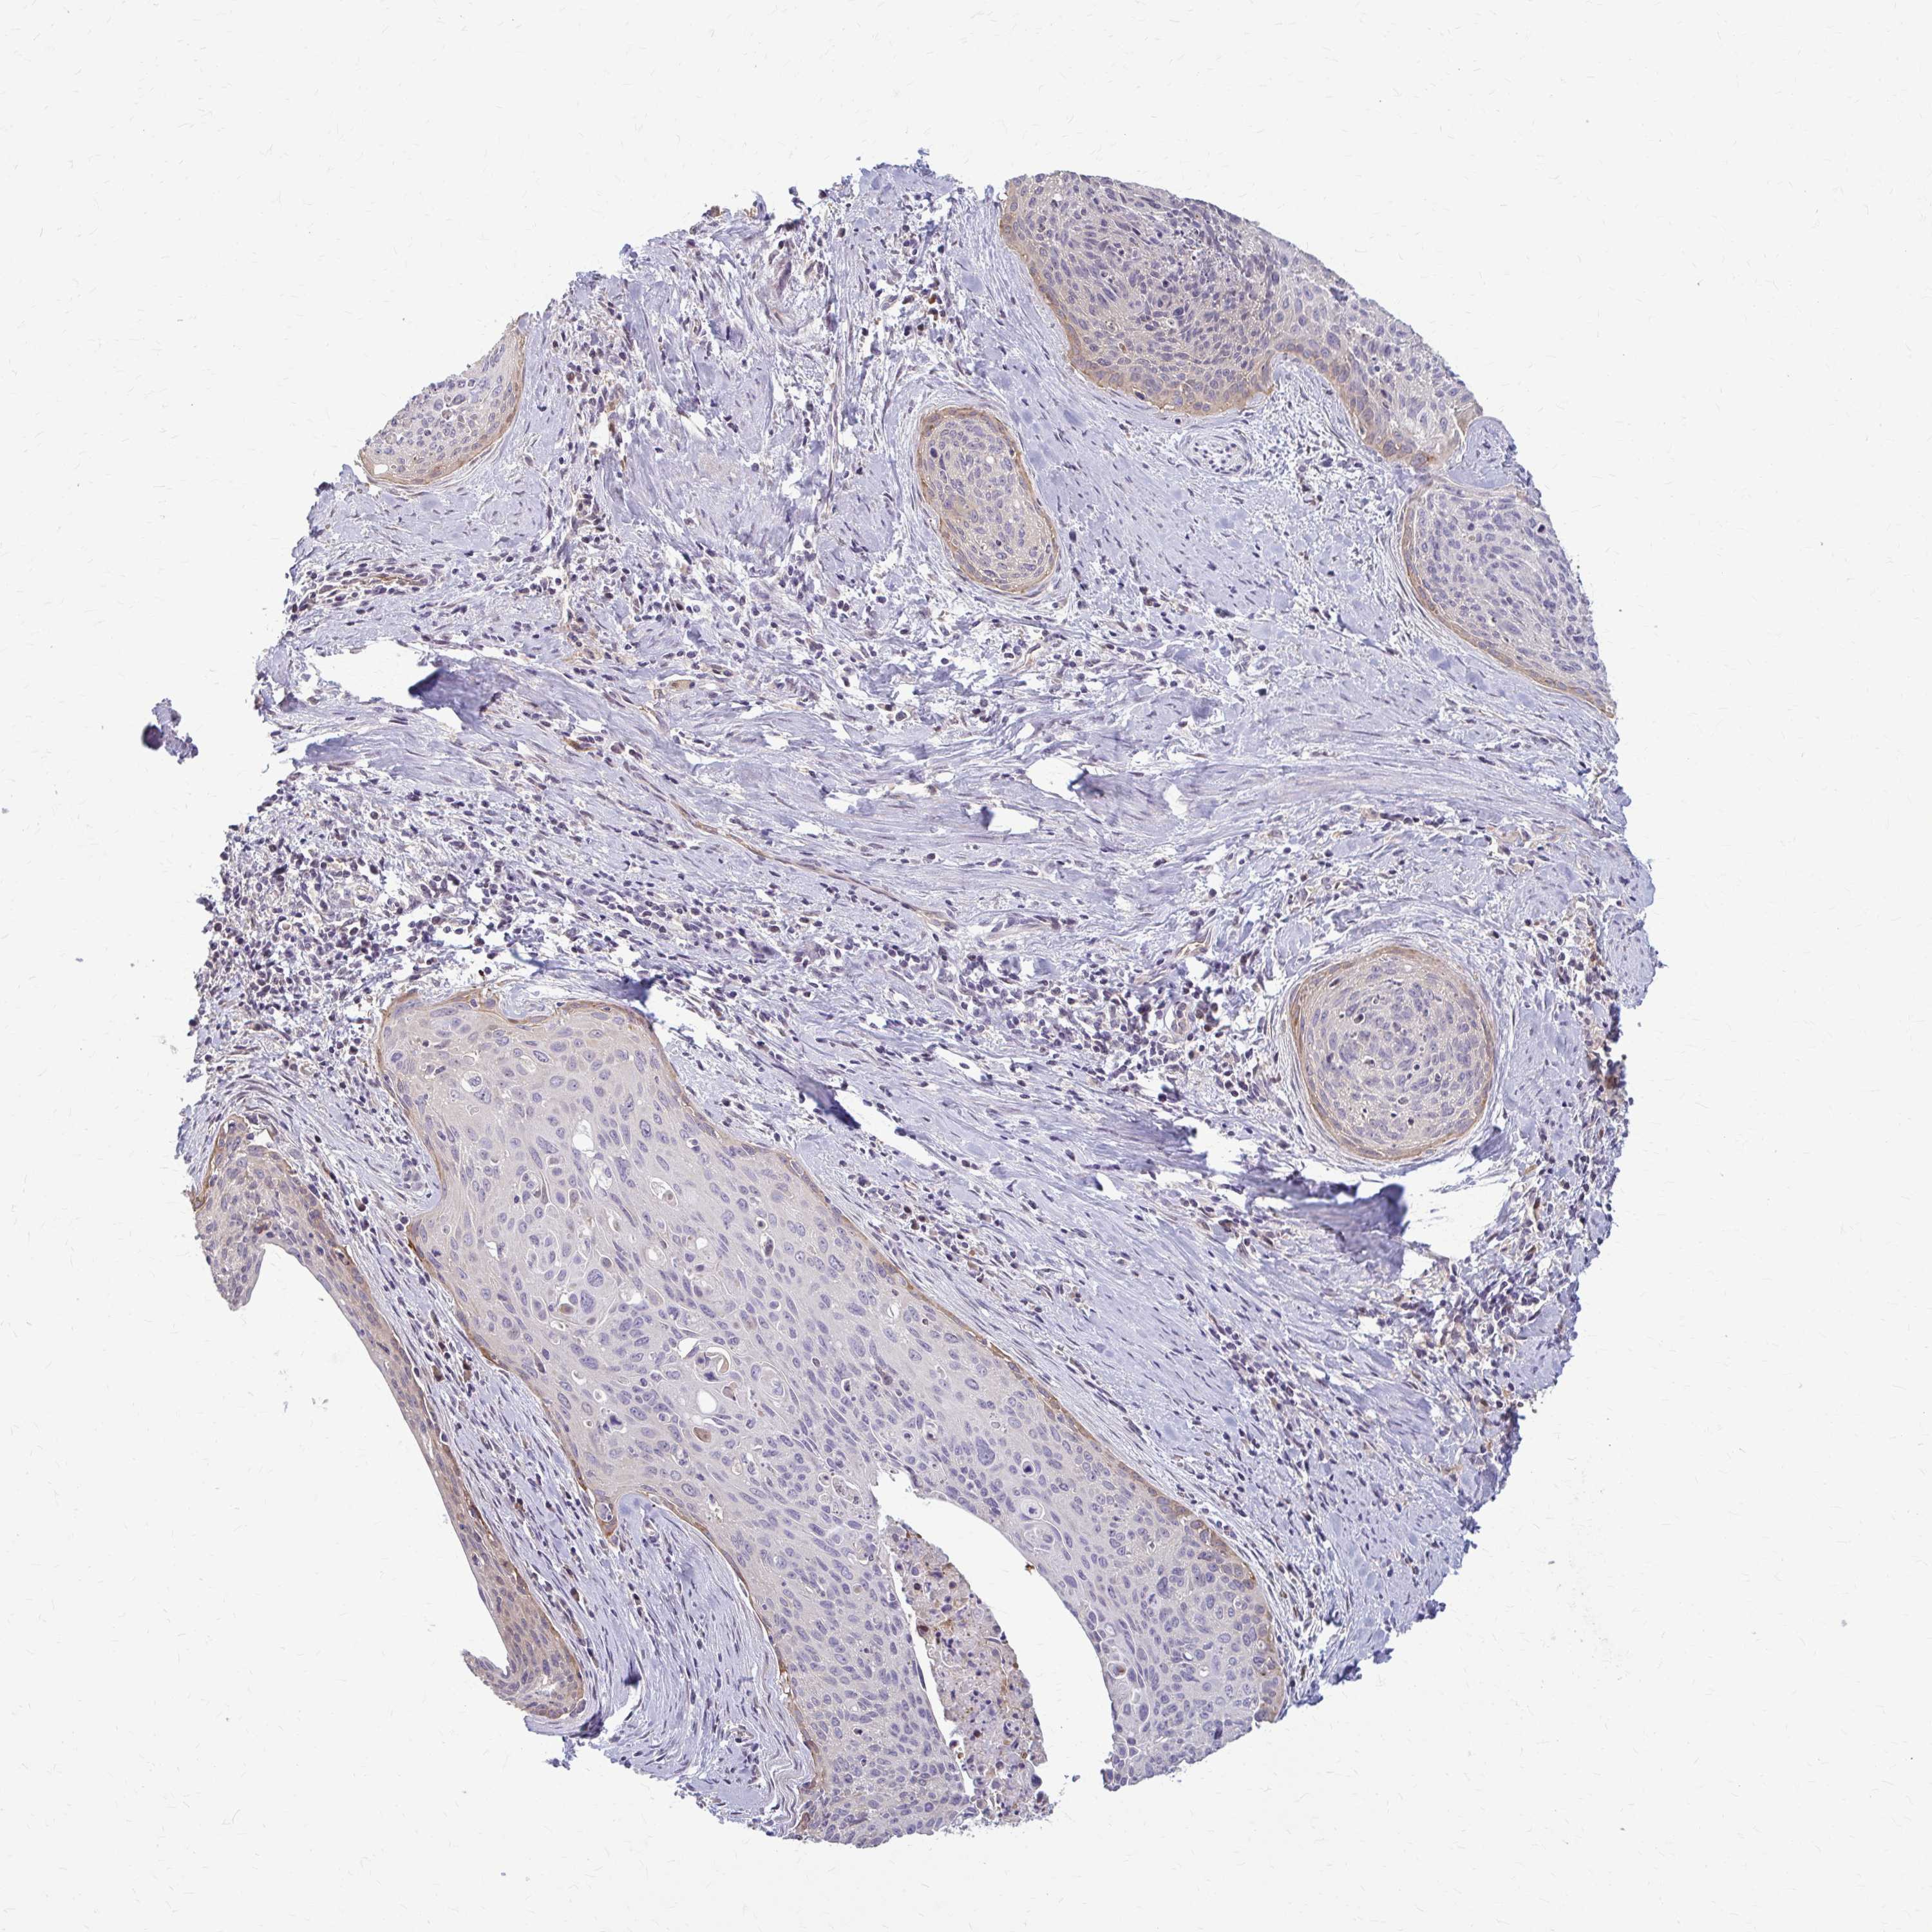

CERVICAL CANCER - Protein expressioni

A mouse-over function shows sample information and annotation data. Click on an image to view it in a full screen mode. Samples can be filtered based on level of antibody staining by selecting one or several of the following categories: high, medium, low and not detected. The assay and annotation is described here.

Note that samples used for immunohistochemistry by the Human Protein Atlas do not correspond to samples in the TCGA dataset.

Antibody stainingi

Antibody staining in the annotated cell types in the current human tissue is reported as not detected, low, medium, or high, based on conventional immunohistochemistry profiling in selected tissues. This score is based on the combination of the staining intensity and fraction of stained cells.

Each image is clickable and will lead to virtual microscopy that enables deeper exploration of all samples and also displays staining intensity scores, fraction scores and subcellular localization as well as patient and tissue information for each sample.

Antibody HPA060755

Staining

High

Medium

Low

Not detected

Intensity

Strong

Moderate

Weak

Negative

Quantity

>75%

75%-25%

<25%

None

Location

Nuclear

Cytoplasmic/membranous

Cytoplasmic/membranous,nuclear

Adenocarcinoma, NOS